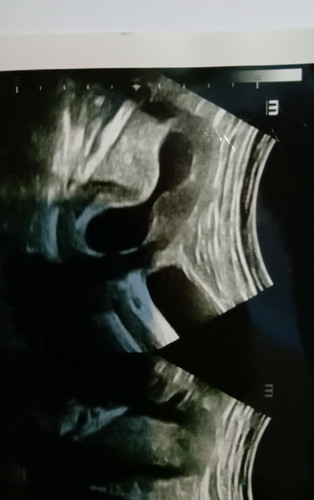

Bun bantu jawab yang punya pengalaman serupa, saya bru sja USG kata dokter bayi nya terlilit tali pusat di leher satu lilitan saat ini usia kandungan msih 21w masih bsa lepas gak yaa bun...??? dokter bilang gk bsa ngelakuin apa apa bunda minta tolong yang punya pengalaman yng sama boleh shre pnglamannya bun... Trimakasih sblmny bunda..#bantusharing #Nanya #bantusharing